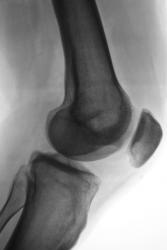

Пациент, врачом хирургом, направлен на рентгенографию коленного сустава в связи с болями. Пациент отмечает, что боли ощущает в течение уже 2-х лет. Ранее производилась рентгенография коленного сустава, однако патологических изменений выявлено не было.

А травмы не было? Латеральнее ММВ как будто бы фрагмент костной плотности. Может быть, болезнь Кёнига? С медиальной стороны щель сустава значительно уже, там же - участок разрежения в мыщелке бедра. На новообразование на первый взгляд не похоже. Без КТ мне трудно судить

Поддерживаю предподожение о б-ни Кенига. Хотя и отсутствует отслоившийся фрагмент, но тем не менее.

В протоколе написал - "состояние после перенесенной болезни Кенига". Хорошо дифференцируется "опустевшее ложе".